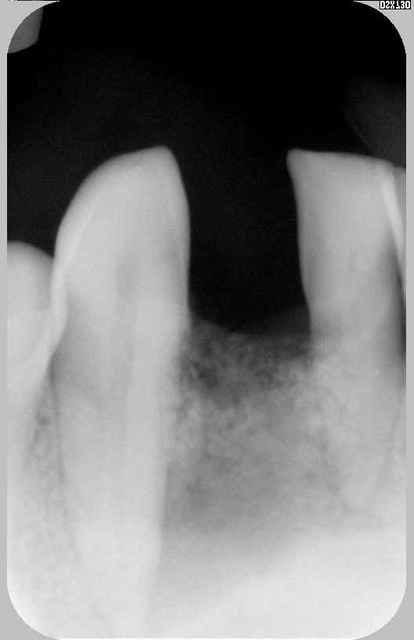

2)sur la densité si on regarde la rétro a postériori idem pour la pano on devine très bien ce pb de densité (surtout quand on le sait cliniquement)

j'essaye de te faire passer pano et scan dès qu'on les aura retrouvé...

rvg en 2011

pseudo réossification autour de mon bricolage si on fait attention faut dire que c'est un beau cône morse (!)

Euh je ne veux pas être négatif mais je dirai plutôt une cratérisation établie; ton os arrivait à la spire distal n°10 (à l'origine) maintenant il est bien en dessous :-(